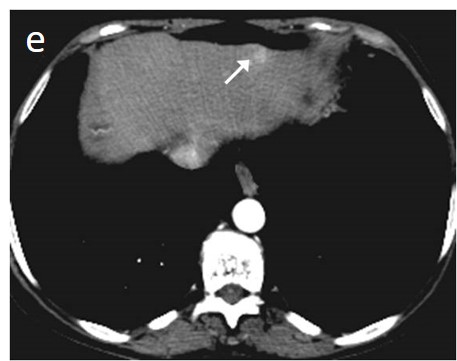

Figure 8. CT perfusion allows the accurate identification and characterization of HCC lesions. In this 69-year-old patient with cirrhosis, a 12-mm nodular lesion in the right liver lobe (arrow) can be easily distinguished from surrounding liver parenchyma on CT perfusion (a–d), with higher values on the Blood Flow (a), Arterial Liver Perfusion (b), and Hepatic Perfusion Index (d) parametric maps and a lower value on the Portal Venous Perfusion (c) map. The lesion is shown on conventional 4-phase CT (e–h), which was performed on the same day as CT perfusion with arterial phase hyperenhancement (f) and wash-out on the portal-venous (g) and delayed phase (h), which corresponds to LI-RADS 5. BF; Blood Flow, ALP; Arterial Liver Perfusion, PLP; Portal Liver Perfusion, HPI; Hepatic Perfusion Index.